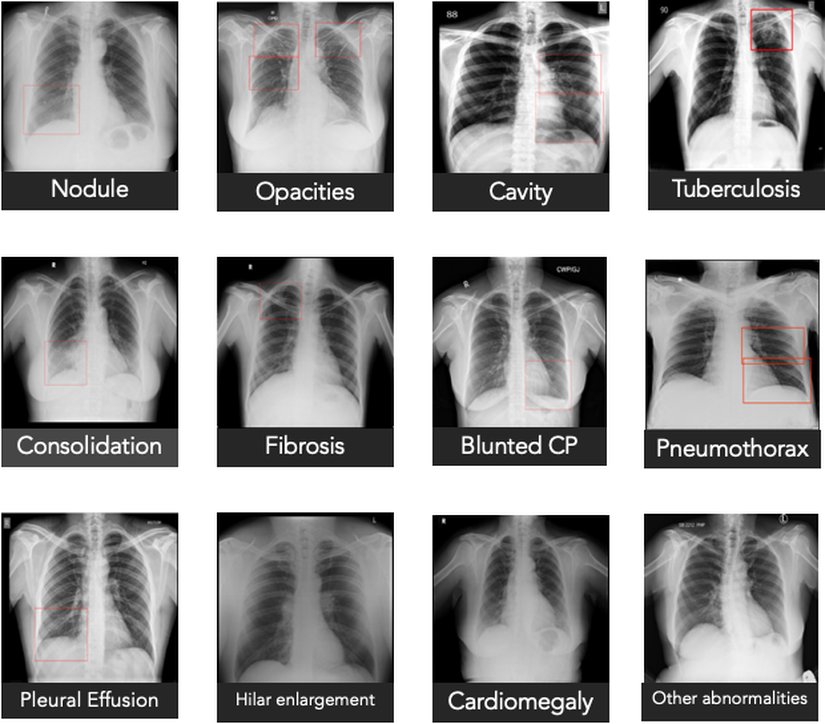

Qure.ai qXR sistemi sık görülen akciğer anomalilerini tespit etmek için derin öğrenme modelleri kullanmaktadır. COVID-19’a uyarlarken uzmanlara danışarak ve literatüre başvurarak COVID-19 pnömonisine ilişkin tipik özellikler değerlendirmeye alınmıştır. Bu bilgiler qXR’ye kodlanmış ve böylece bu enstrüman bu tarz bir görüntüyü taradığında covid-19 enfeksiyonu riskine ilişkin hesaplamalar yapacak duruma getirilmiştir. On bir görüntüyü kapsayan bir ön geçerlik çalışması COVID-19 hastalarının %95 hassasiyetle tespit edilebildiğini göstermiştir.